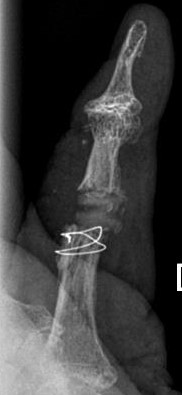

Einsatz einer Silikon-Endoprothese in das Daumenendgelenk, obwohl die Prothese für das Mittelgelenk konstruiert wurde.

Das Daumensattelgelenk wurde in gleicher Operation mit einer Resektions-/-suspensionsarthroplastik behandelt.